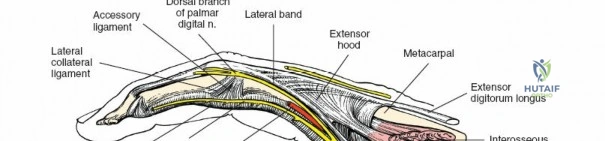

A thorough understanding of the intricate anatomy and biomechanics of the flexor tendon system is non-negotiable for any surgeon employing a volar approach. The digital flexor system comprises the Flexor Digitorum Superficialis (FDS) and Flexor Digitorum Profundus (FDP) tendons. The FDP tendon originates from the ulna and interosseous membrane, inserting onto the volar base of the distal phalanx, primarily responsible for DIP joint flexion. The FDS tendon originates from the medial epicondyle, ulna, and radius, typically bifurcating around the FDP in the region of the proximal phalanx (Camper's chiasm) before inserting onto the middle phalanx, primarily flexing the PIP joint.

Within the fibro-osseous tunnel, these tendons are enveloped by a synovial sheath that facilitates smooth gliding and nutrition. The integrity of the pulley system, composed of annular (A) and cruciate (C) ligaments, is critical for preventing tendon bowstringing and maintaining efficient mechanical advantage. Typically, five annular pulleys (A1-A5) and three cruciate pulleys (C1-C3) are described in each finger. The A1 pulley is at the metacarpophalangeal (MCP) joint level, A2 at the proximal phalanx, A3 at the proximal interphalangeal (PIP) joint, A4 at the middle phalanx, and A5 at the distal interphalangeal (DIP) joint. The A2 and A4 pulleys are considered the most critical for preventing significant bowstringing.

The digital neurovascular bundles (NVBs) run along the radial and ulnar sides of each digit, volar to the collateral ligaments, providing sensation and vascularity. Proper identification and protection of these bundles are paramount during any volar dissection. Proximally, the median nerve gives rise to recurrent motor branches to the thenar muscles and sensory branches to the thumb, index, middle, and radial half of the ring finger. The ulnar nerve supplies the hypothenar muscles, adductor pollicis, and interossei, along with sensory innervation to the little finger and ulnar half of the ring finger. The palmar arches (superficial and deep) provide critical vascular supply to the hand.

The palmar fascia, located superficial to the flexor tendons in the palm, is a dense aponeurosis important in conditions like Dupuytren's contracture. This fascial layer can obscure deeper structures and must be carefully managed during deep palmar dissection. The thenar and hypothenar eminences, as well as the transverse palmar crease, serve as important surface landmarks for guiding incisions and identifying underlying structures. The vincula tendinum (longus and brevis) are mesotenon-like structures that provide vascular supply to the flexor tendons within the sheath, and their preservation, where possible, is beneficial.